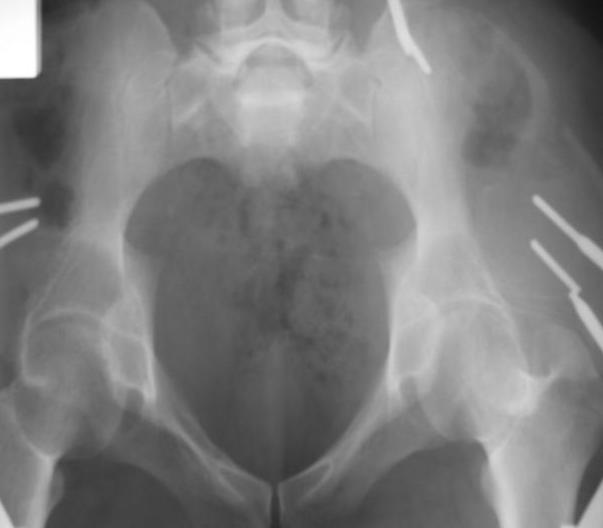

Поступил пациент после кататравмы (упал с высоты 4м). После обследования установлен Ds: Сочетанная травма. ЗТГК перелом 5-6 ребер справа. Ушиб левого леогкого. Оскольчатый перелом крыла подвздошной кости слева, со смещением. в экстренном порядке выполнена операция о/синтез таза стержневым аппаратом. Снимки прилагаются. Пациент со 2-го дня стал ходить без костылей. Из анамнеза жизни у пациента имеется гепатит В и С, с 1998г. употребляет наркотики (героин 1г в день нормальная доза). На контрольных снимках таза в аппарате смещение отломков сохраняется, да еще и стержни сломались. Подскажите ув.коллеги, как поступить в данной ситуации: оставить все как есть или добиваться репозиции в аппарате, или планировать на открытую репозицию. На сегодняшний день пациент стабилен, по анализам компенсирован. Принимает героин по другому справиться не может. С ув. Андрей

Уважаемый Андрей, у пациента имеется перелом передней колонны,и после наложения аппарата положение отломков ухудшилось. возможно не из-за ваших действий а за счет тяги четырехглавой мышцы. Обе ости настойчиво будут тянуть крыло вниз.

C момента травмы прошло ровно 10 дней. Да Максим, вы как в воду глядели, у стержней появились признаки воспаления. Аппарат демонтирую.